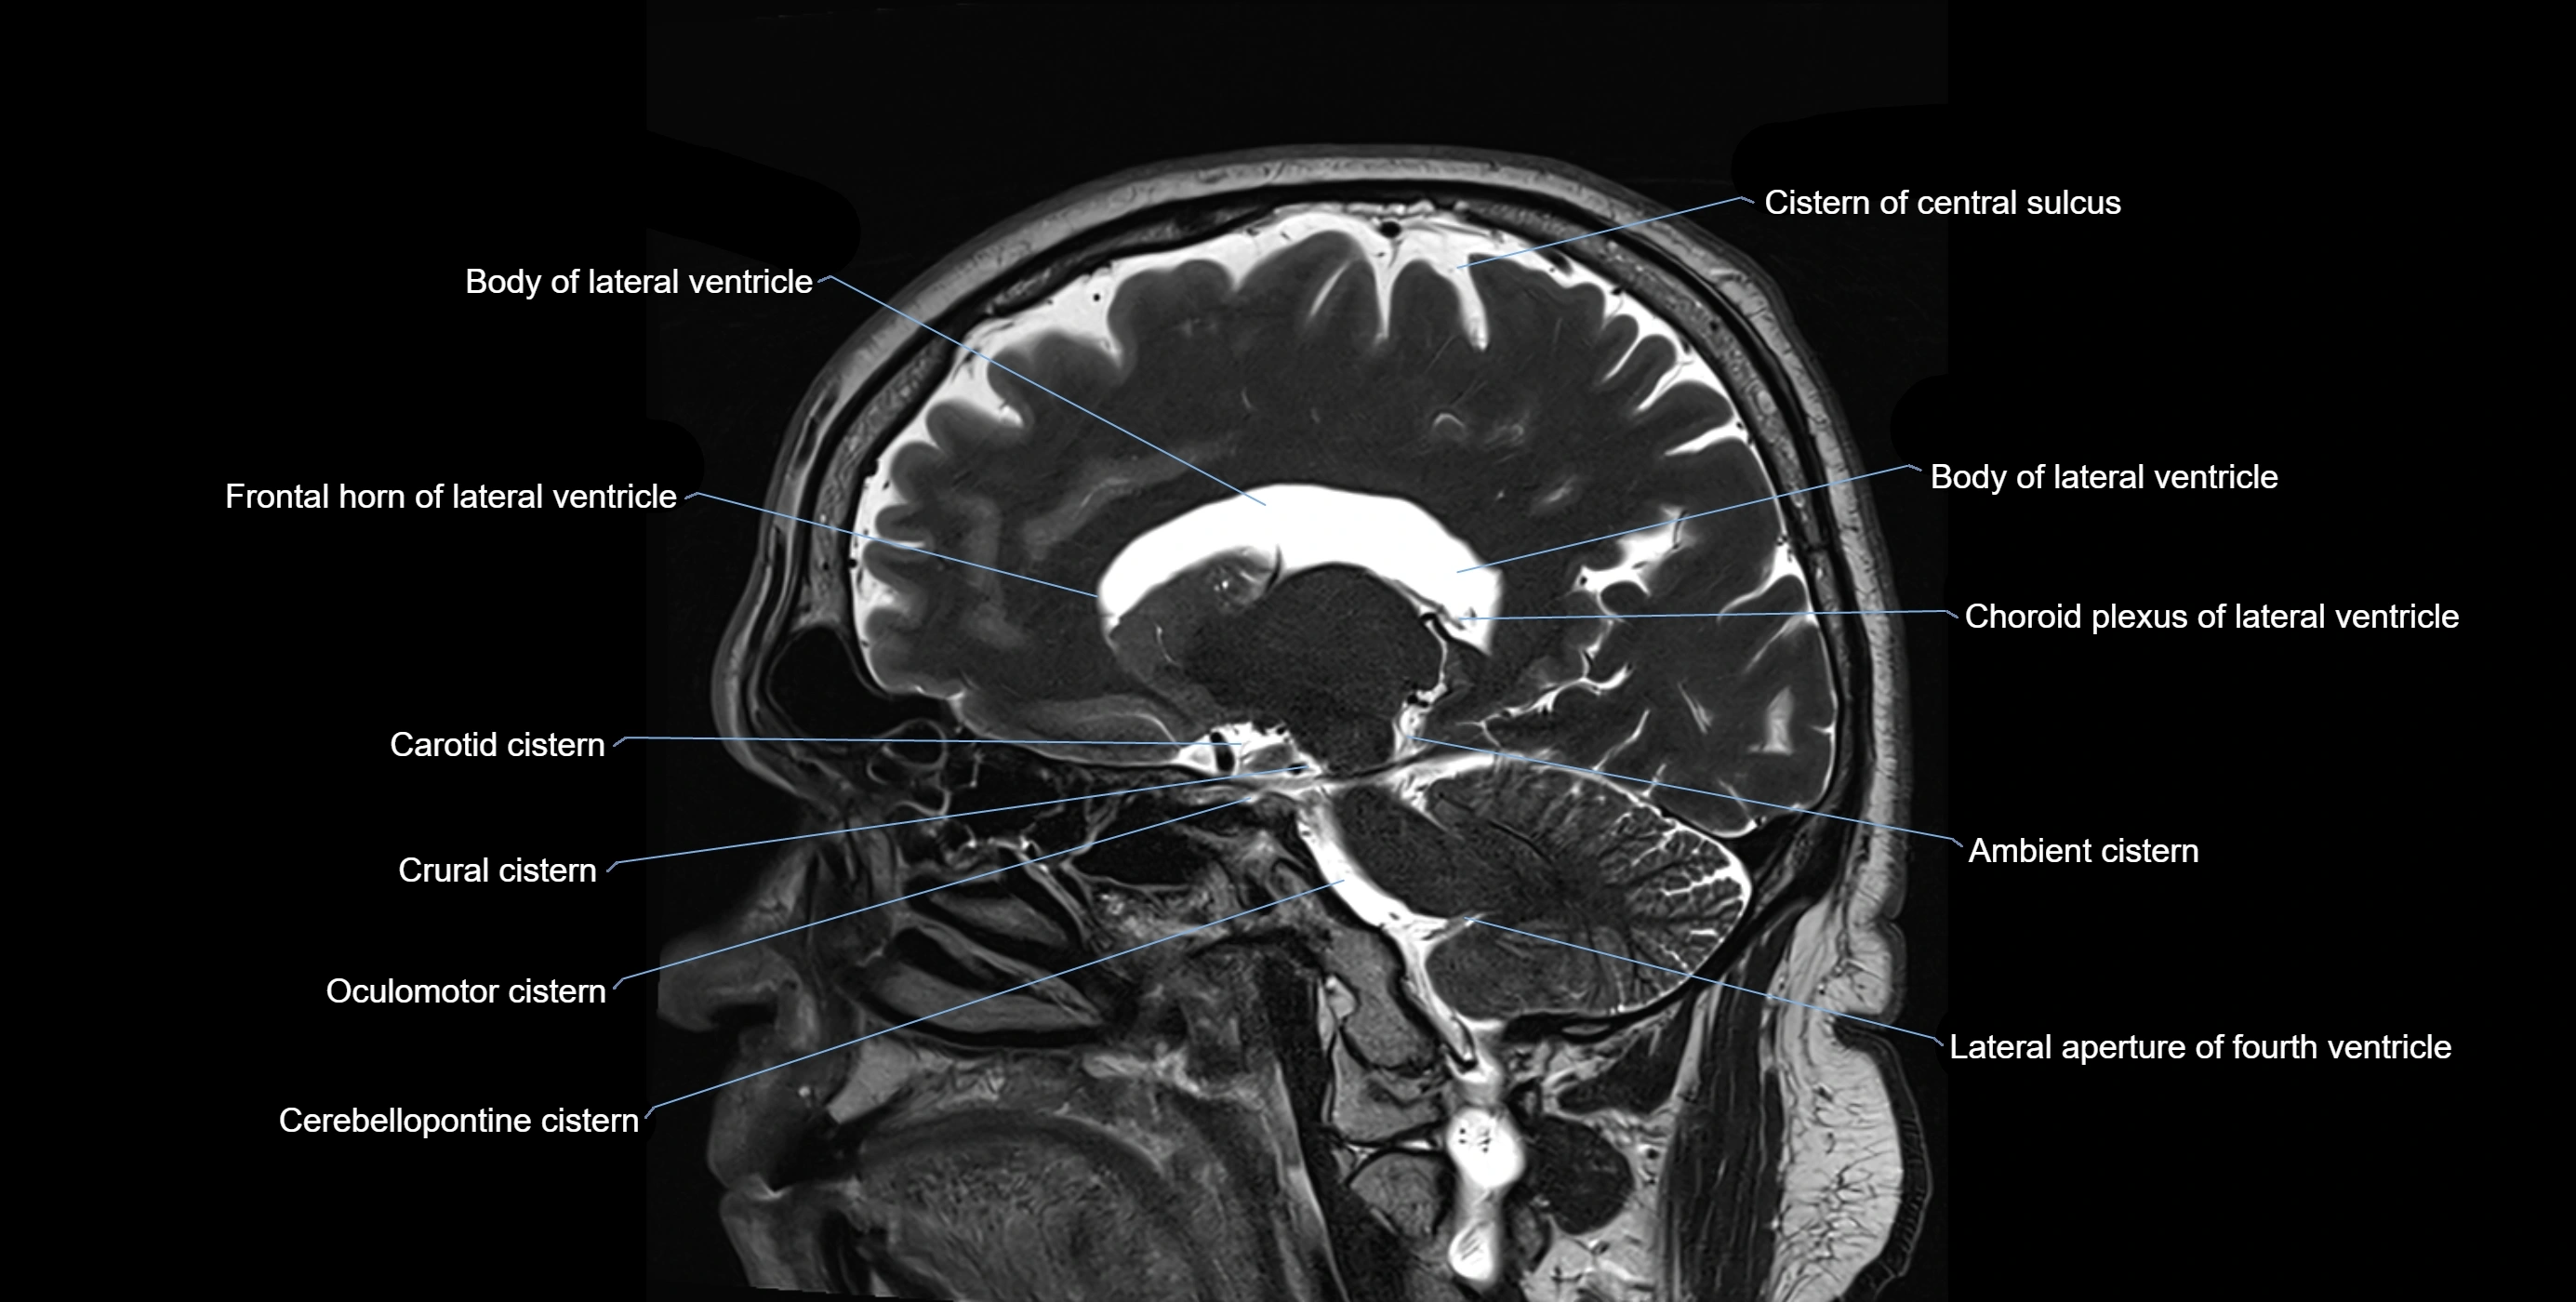

MRI images

image